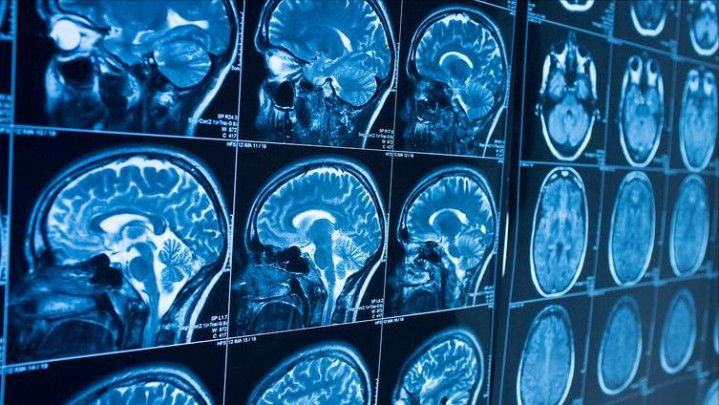

脑梗,又称脑梗死,是由于脑部血管被血栓堵塞,导致脑组织缺血、缺氧而激发的疾病。65岁以上东说念主群是脑梗的高发东说念主群,而这一年级段的血管一样存在不同进程的动脉硬化。动脉硬化让血管壁失去弹性,血流变慢,血液更容易在窄小的血管处变成血栓。再加上高血压、糖尿病、高血脂等基础疾病,脑血管的“危境整个”也随之大幅增多。